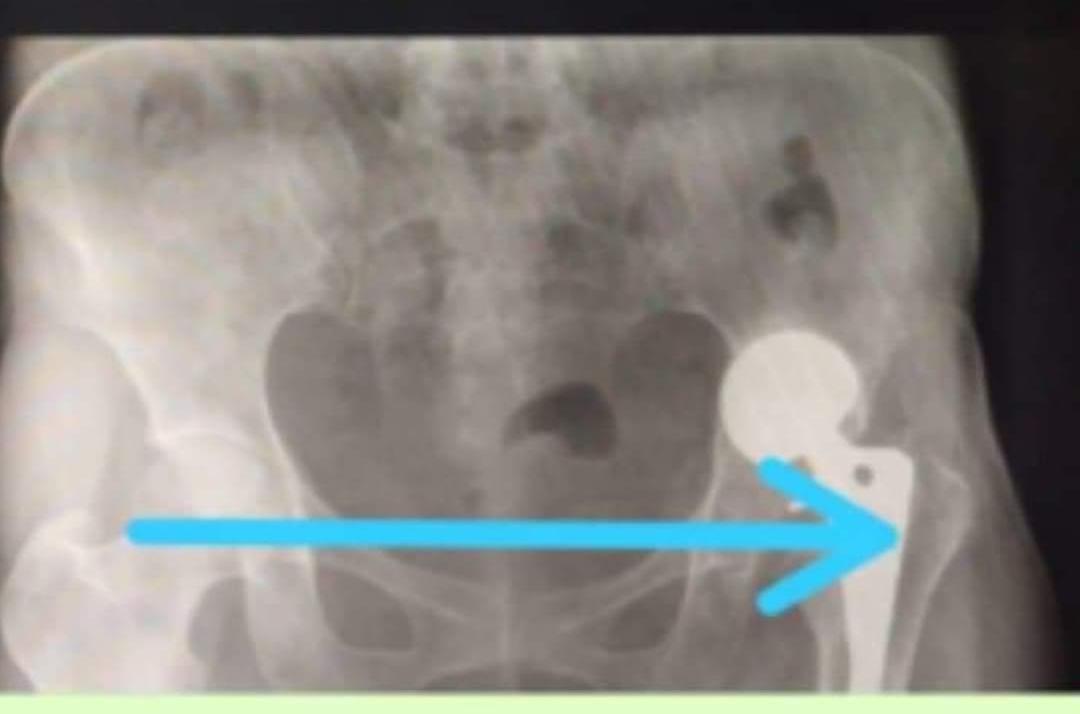

Para ese entonces, me operaron y colocaron una prótesis incorrecta en la cadera, que con el paso del tiempo se ha vencido y me está provocando severas lesiones en el área, lo cuál me causa dolores de fuerte intensidad y me impide caminar.

Los médicos me han diagnosticado signos de protusión acetabular lo cual amerita nueva intervencion quirúrgica, para el recambio de endoprótesis de cadera izquierda cementada, que deben realizarme lo más pronto posible, debido a que con el paso de los días los huesos se siguen dañando y hasta corro el riezgo de sufrir daños irreparables.